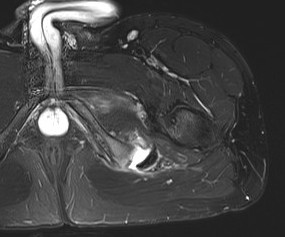

MRI

Ischial tuberosity avulsion 3Ischial tuberosity avulsion 2